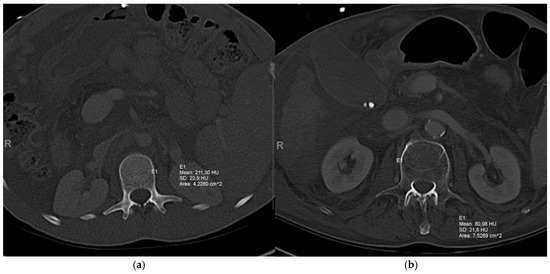

2.2. Assessment of Vertebral Trabecular Attenuation at the First Lumbar Vertebra